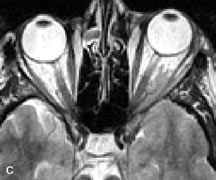

Lymphomas have MRI characteristics similar to those of inflammatory lesions in that they are hypointense to fat and isointense to muscle on T1-weighted images (Fig. 22). They may appear hyperintense to fat on T2-weighted images, perhaps owing to less fibrosis than that seen in orbital inflammatory pseudotumor, although this is not a consistent finding.31,50,66 Lymphoid tumors typically enhance moderately after contrast injection. Unfortunately, studies have shown that tumor density and homogeneity are similar between inflammatory and malignant orbital infiltrates, and MRI cannot differentiate these lesions.72,73

Fig. 22. A and B. T1- and (C) T2-weighted MR scans demonstrate a poorly defined multicompartmental mass enveloping the lateral rectus, superior rectus, and levator palpebrac superioris muscles. The lesion is isointense to brain on T1- and T2-weighted scans, as is typical for highly cellular neoplasms. D. Postcontrast fat-suppressed T1-weighted scan demonstrates intense enhancement of the infiltrating intraconal and extraconal tumor.